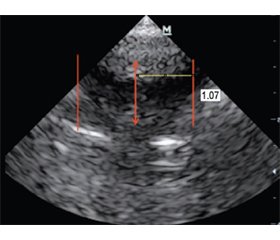

68. I. Oulad Abdennabi, J. Bakker. Ultrasound measurements of the lateral ventricles in neonates: A comparison of multiple measurements methods. In: Ultrasound measurements of the lateral ventricles in neonates: A comparison of multiple measurements methods. 2014:1-9. doi: 10.1594/ecr2014/C-1557.